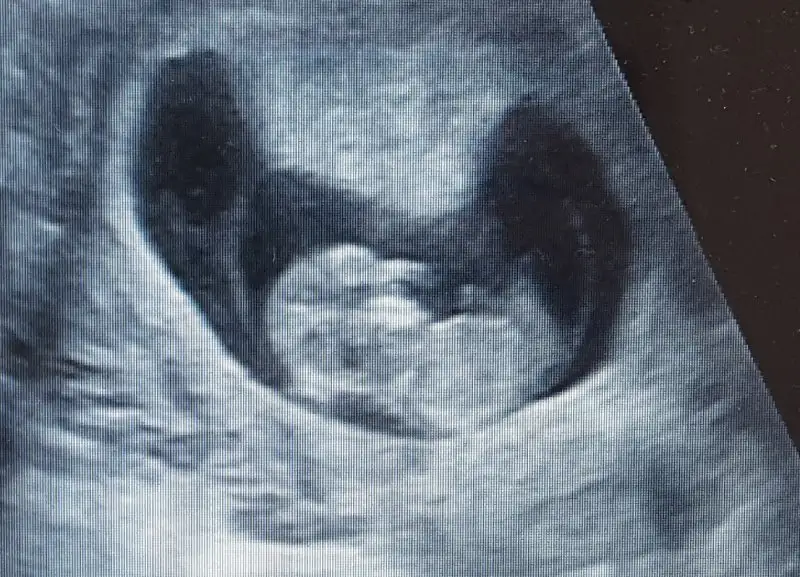

12h 1gun ama resimde hiçbir şey belli değil aslinda baş ve popo mesafesi ölçerken daha netti görüntü ama oresmi vermemiş zarfı bir açtım ki bu resim varBen hiçbir şey anlamadım canım valla kaç haftalık burda ki

Bazen benim oglum yapio telefondan sacma sapan resimler cekio doktordan aynn ole ne yamaya calismis anlasilmio12h 1gun ama resimde hiçbir şey belli değil aslinda baş ve popo mesafesi ölçerken daha netti görüntü ama oresmi vermemiş zarfı bir açtım ki bu resim var

Erkek gibi sanki canım orda bir çıkıntı mi var yoksa beyaz bir leke mı emin değilim ama tahminim erkek canım :)Anlayan varsa tebrik edicem valla Eki Görüntüle 2093038

Maşallah canım sağlık olsun önümüzdeki günlerde belli eder cinsiyetini minnoşHayırlı cumalar arkadaşlar.Dr.dan geldim tam 12 haftalık olmuşuz gayet iyi dedi cinsiyeti için erken dedi ama şu ultrason da burada daha önce daha küçük haftası olan görüntüler gibi bir görüntüyü pek göremedim çok gıcık oldum Dr karın bölgesi fazla yağlı ondan net değil dedi hiç tatmin edici bir cvp degil bende şöyle güzel bir fotoğraf verirde kızlar tahmin eder diye bekliyordum sonuç elimdeki den hiçbir şey anlaşılmıyor![]()